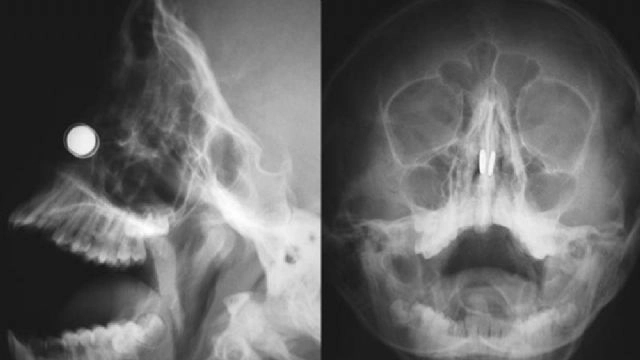

Bir süre önce her iki burun deliğine saat piline benzeyen küçük iki manyetik disk sokan 11 yaşındaki erkek çocuğunun, burnuna sıkışan mıknatısları çıkarmak için Doç. Dr. Kadir Çağdaş Kazıkdaş başkanlığında gerçekleştirilen operasyon literatüre geçti.Konuyla ilgili açıklamalarda bulunan Yakın Doğu Üniversitesi Hastanesi'nde Doç. Dr. Kadir Çağdaş Kazıkdaş, en güçlü mıknatıslardan olan neodyum mıknatıslarının buruna girer girmez çocuğun burun direği etrafında birbirine yapıştığını açıkladı. Çocuğun mıknatısları burnuna soktuktan yaklaşık altı saat sonra dayanılmaz bir ağrı, burun kanaması ve burun içinde kabuklanma şikayetleri ile hastanenin acil servisine getirildiğini ifade eden Doç. Dr. Kazıkdaş, yapılan ilk müdahalede mıknatısların halen çocuğun burnunda olup olmadığının kesin olarak anlaşılamadığını, burun içerisinde de kanamaya bağlı çok fazla kabuklanma olduğunu, bu arada çocuğun duyduğu ağrı ve korku nedeniyle doktorların müdahale girişimlerini de engellediğini söyledi. Doç. Dr. Kazıkdaş daha sonra hastanın Kulak, Burun Boğaz Polikliniği'ne sevk edilerek, yüz röntgeninin çekildiğini, böylece burun içerisinde birbirine kenetlenmiş olan mıknatısların tespit edilebildiğini söyledi.DOÇ. DR. KAZIKDAŞ; GELENEKSEL CERRAHİ ALETLER İLE ÇIKARMAYI DENEDİM AMA İMKANSIZDIHızlıca ameliyathaneye alınan çocuğa genel anestezi verilerek bu esnada mıknatısları çıkarmanın bir yolunun arandığını söyleyen Doç. Dr. Kadir Çağdaş Kazıkdaş; "Çocuk septal perforasyon dediğimiz, burun direğinde küçük bir delik oluşması riski altındaydı. Aynı zamanda, eğer en kısa zamanda mıknatıslar çıkarılmazsa, burun kıkırdağında kangren ya da doku ölümü gerçekleşme olasılığı da vardı" dedi.Geleneksel cerrahi aletlerle mıknatısları çıkarmayı denediklerini ama bu şekilde sonuç alamadıklarını ifade eden Doç. Dr. Kadir Çağdaş Kazıkdaş, son olarak burun içinde kenetlenmiş olan mıknatısları kaldırıp çıkarmak için burun dışından sıradan mıknatıslar kullanmayı düşündüklerini ifade ederek şöyle devam etti; "Bu yöntem ile sol taraftaki mıknatısı kolaylıkla çıkarmayı başardık. Ardından ikinci mıknatısı çıkarmak da saniyeler sürdü. Çocuğun burun kıkırdağında oluşan hasarlı bölgeye ve travmatize olan dokulara yapay yama uygulandı. İlerleyen dönemdeki iyileşmeyi desteklemesi için silikon burun ateli de takıldı. Atel operasyon sonrasında on gün boyunca hastanın burnunda takılı kaldı."Doç. Dr. Kadir Çağdaş Kazıkdaş, çocuğun altı ay sonraki takip muayenesinde, kalıcı hasar emaresi bulunmadığını ve rahatça burundan nefes alabildiğinin gözlemlendiğini belirtti. Doç. Dr. Kadir Çağdaş Kazıkdaş yaptığı açıklamada, mıknatıs kullanımının bir moda çılgınlığı olarak giderek popülerleşen bir olay haline geldiğini ve maalesef yetişkinlerde bile bu tür yabancı maddelerin kullanımı ile yaşanan olumsuz durumlarla daha sık karşılaşılmaya başlandığını söyleyerek, ailelerin mıknatıs ve düğme pilleri, çocukların ulaşamayacağı yerlerde saklamaları gerektiği konusunda uyarılarda bulundu. Bu tür objelerin küçük boyutta olmalarına rağmen şaşırtıcı derecede güçlü bir çekim kuvvetleri olduğunu ifade eden Doç. Dr. Kadir Çağdaş Kazıkdaş, takı ya da estetik amaçlar için kullanılabilecek olan mıknatısların potansiyel tehlikeleri ile ilgili daha büyük çocukların da bilgilendirilmesi gerektiğini söyledi.ÇOCUĞUN BURNUNDAKİ MIKNATISLARI ÇIKARMA YÖNTEMİ, DIŞ BASINDA DA YER BULDUYakın Doğu Üniversitesi Hastanesi Kulak Burun Boğaz Anabilim Dalı ekibinin, 11 yaşındaki çocuğun burnundaki mıknatısları çıkarma yöntemi, dış basında da yer buldu.Kanada haber sitesi CTV News, konuyla ilgili haberi "Doktorlar, çocuğun burnunda sıkışıp kalmış mıknatısları çıkarmak için mükemmel bir yol buldular", Amerikan radyo kanalı ve haber sitesi National Public Radio ise "Bir Çocuğun Burnuna Mıknatıs Sıkıştığında, Doktorlar Hassas Davranmak Zorundadır" başlığıyla duyurdu.The New England Journal of Medicine ise bu konu hakkında yayınladığı makalede, mıknatısların çok uzun süreden beridir çocuklar için bir sağlık sorunu oluşturduğunu, 2013 yılında Annals of Emergency Medicine'da yapılan çalışmada, 2001 ve 2002 yılları arasında, 21 yaş altı 22.500'den fazla kişide mıknatısla alakalı yaşanmış kaza tespit edildiği, mıknatısların vücuda ağır hasar verebileceği, hatta ölüme neden olabileceğinin göz ardı edilmemesi gerektiği ifade edilerek, Kıbrıs'ta yaşanan vakada doktorların sorunu dahiyane bir şekilde çözüme dönüştürmeyi başardıklarını yazdı.Norfolk'daki The King's Daughters Hastanesi Pediatrik Kulak Burun Boğaz Bölümü yöneticisi Dr. Craig Derkay ise "Hemen hemen hergün çocukların kulaklarından, burunlarından ve boğazlarından bir şeyler çıkarıyoruz. Özellikle saatlerde ve oyuncaklarda bulunan düğme pillerden endişe duyuyoruz. Shots'un 2012 de belirttiği gibi bunlar yanmalara ve doku ölümüne yol açabilirler. Neyseki burnunda mıknatıs sıkışan çocuğun durumu güzel bir şekilde sona erdi." dedi.(Hüseyin Çakmak/İHA)